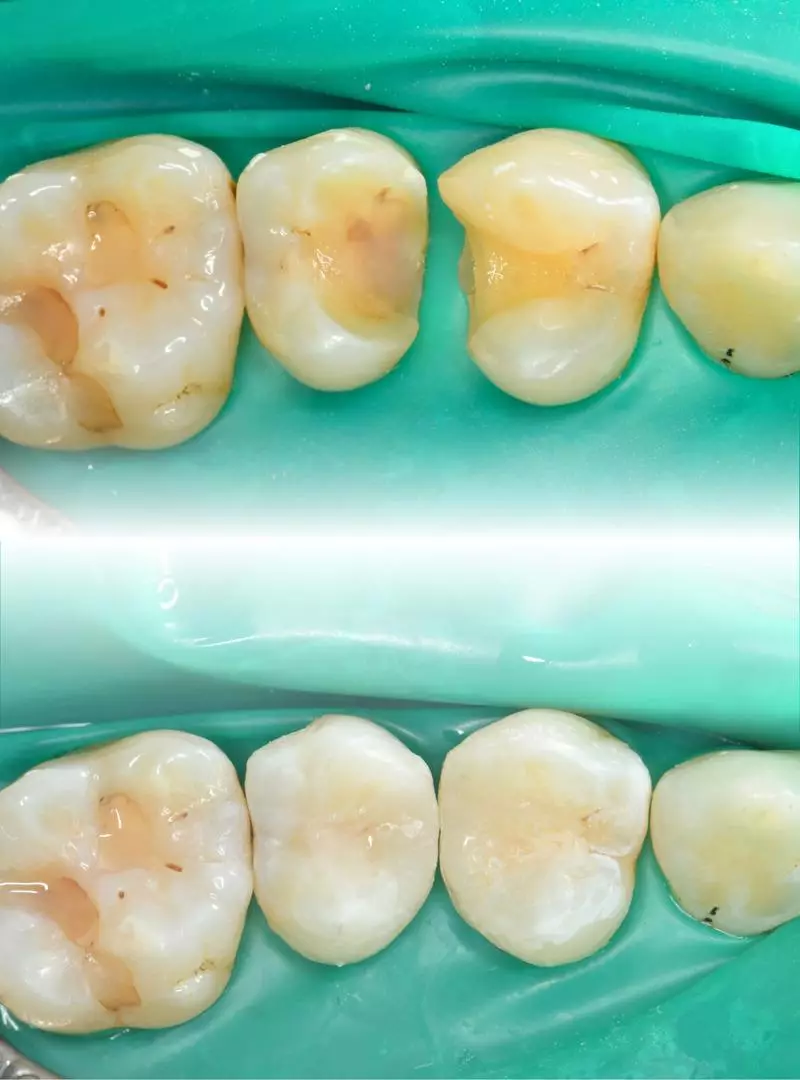

相比全冠修復,更能最大程度保留原來齒質,完成修型(上)陶瓷嵌體修復後(下)